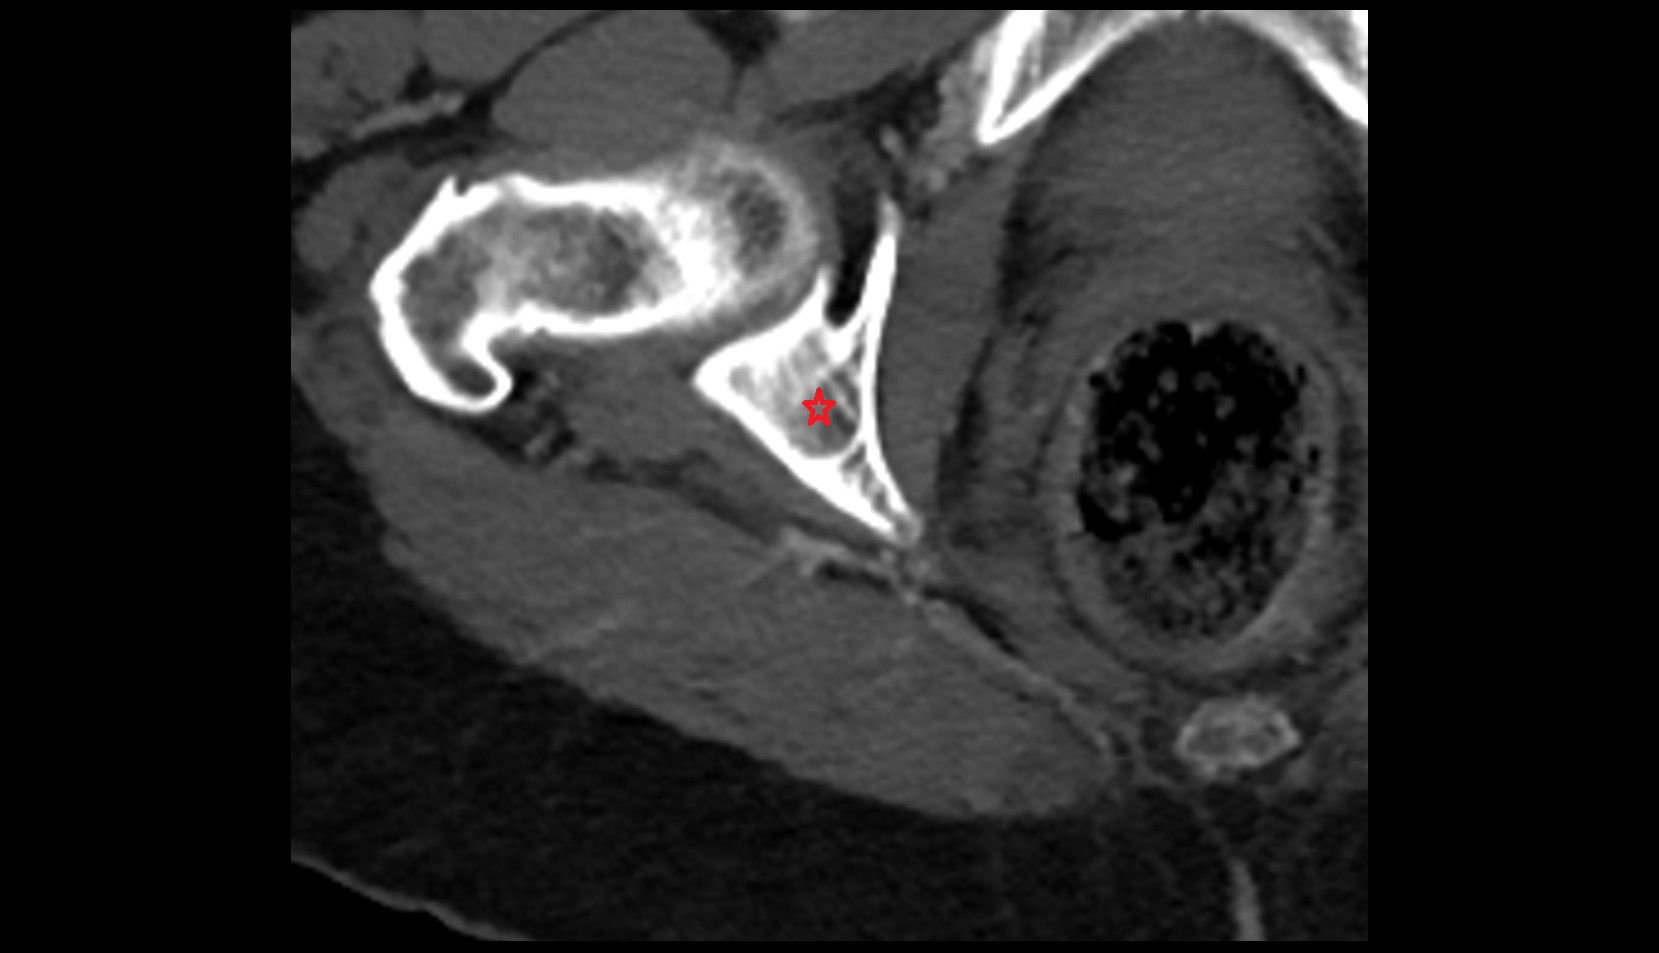

- Corpus cavernosum

- Corpus spongiosum

- Bulb of Penis

- Crus of penis